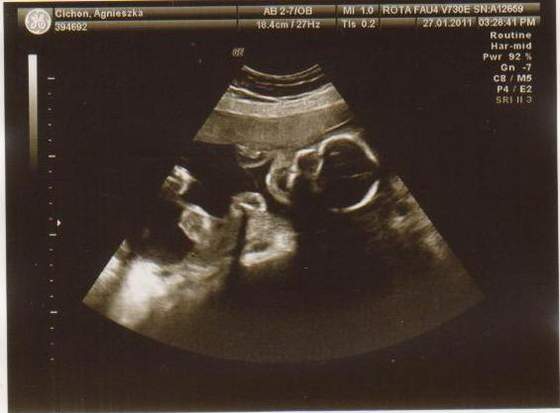

cześć dziewczyny to i ja chciałabym do Was dołączyć, właśnie znalazłam to forum. Mieszkam w Irlandii od 4 lat i mam synka 21 miesięcy, a teraz jestem w 28 tc bliźniaczej :-) dwie dziewczynki dwujajowe :-) też mnie trochę przeraża poród bliźniaków ale trzeba jakoś urodzić ;-) Pierwszy poród miałam jak marzenie szybko, sprawnie i nawet bez znieczulenia, mam nadzieję że i tym razem bęzie podobnie.

Hej podwojne mamunie:-)Ja juz rozpakowana dawno mamusia dubeltowka.Gratuluje wam serdecznie i witam w gronie tych wybranych hihiNiczego sie nie bojcie.Ciaxa blizniacza jest pod specjalna opieka.Czekaja was czeste wizyty w szpitalu i czeste ogladanie maluszkow na usg :-)